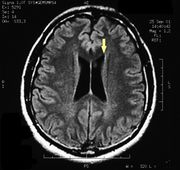

| 17:30, 26 February 2023 | Pineal cavernoma pre surgery 1.jpeg (file) |  |

128 KB | 1 | |